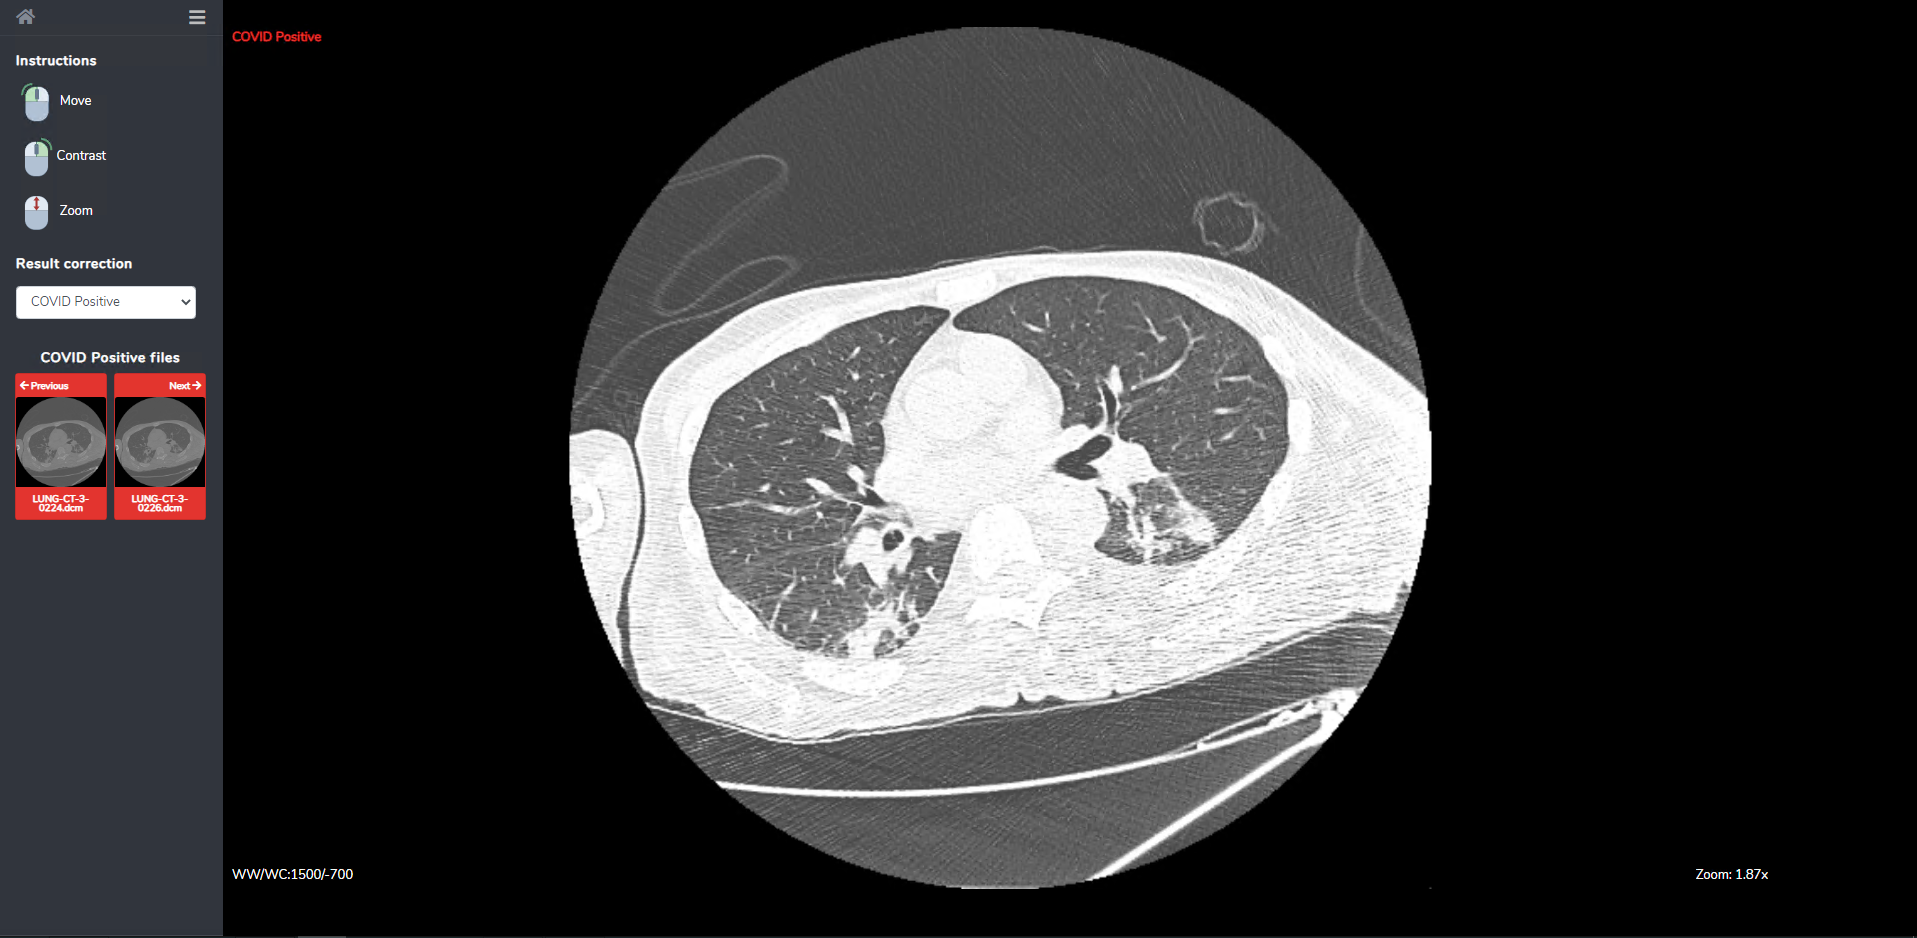

Because the models may not achieve perfect accuracy, a single slice inspection screen is provided, where radiologists can inspect more closely the result of the classification. It also features a restricted set of image manipulation tools (move, contrast, zoom) for aiding the user to make a correct diagnosis (Fig. 8).

Refer to caption

Figure 8: The slice inspection screen. In this screen the user can inspect each single slice and the AI models’ decisions.